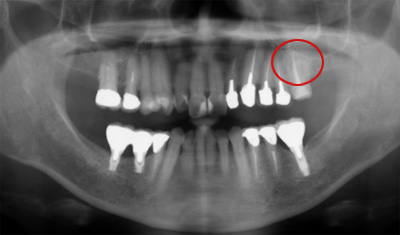

下のレントゲンは昨日、左上奥歯のお痛みが主訴でいらした患者さんです。赤丸の部位です。歯科用レントゲンではわかりずらいです。

歯科用パノラマレントゲン